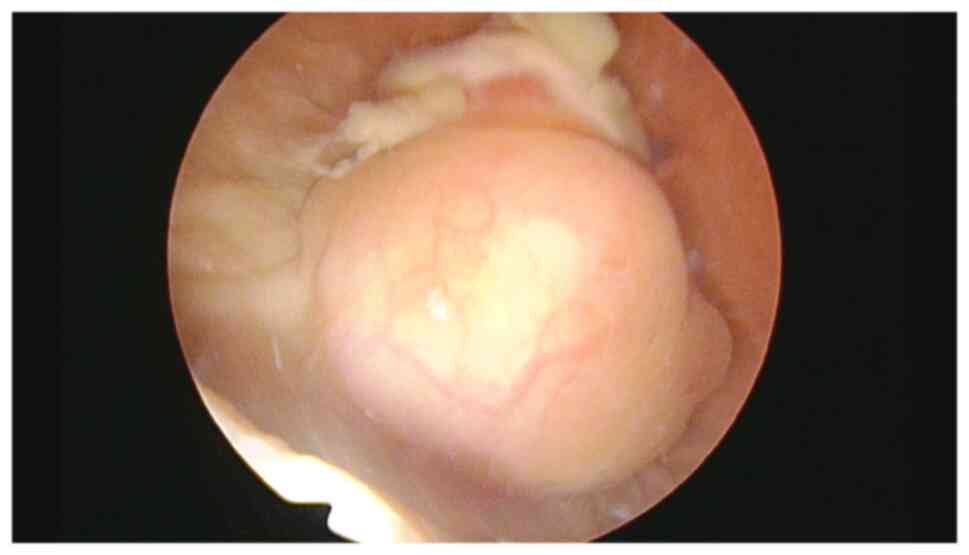

Inflammatory myofibroblastic tumor of the urinary bladder with FN1‑ALK gene fusion: A case report

Inflammatory myofibroblastic tumors (IMTs), which are rare tumors, exhibit myofibroblastic differentiation, often with anaplastic lymphoma kinase (ALK) gene rearrangements. A subset of IMTs identified in the urinary tract have been shown to harbor a fibronectin 1 (FN1)‑ALK gene fusion. In this case report, a case of an IMT with FN1‑ALK fusion in the urinary bladder was presented, and its clinicopathological characteristics were reviewed. A 45‑year‑old female was referred to Chungbuk National University Hospital with gross hematuria. Cystoscopy revealed a solid mass in the bladder. The patient subsequently underwent transurethral resection of the lesion. The mass comprised stellate and spindled myofibroblastic cells that were arranged in loose fascicles, with a myxoid background and a mixed inflammatory infiltrate. Immunohistochemical analysis revealed that the tumor cells were positive for vimentin, cytokeratin AE1/AE3 and ALK, and focal‑positive for desmin. Targeted next‑generation sequencing was subsequently employed to identify the FN1‑ALK fusion. To date, the patient has undergone outpatient follow‑up for 18 months, with no signs of tumor recurrence. To conclude, in total, FN1 has been identified as an ALK fusion partner almost exclusively in cases of genitourinary IMTs [13 bladder IMTs (including the present case) and two uterine IMTs]. In the present case, the FN1‑ALK fusion was found to involve ALK exon 19 and FN1 exon 23. By contrast, the majority of the other IMTs with an ALK fusion have involved ALK exon 20, whereas ALK fusion involving ALK exon 18 or 19 has been reported only in genitourinary IMTs. Therefore, the FN1‑ALK fusion involving ALK exon 18 or 19 may be specific to a subset of IMTs arising in the urinary bladder.